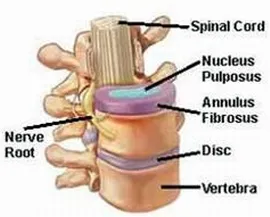

Nucleoplasty – Phương pháp phẫu thuật xâm lấn tối thiểu điều trị thoát vị đĩa đệm

Theo số liệu thống kê tại Singapore vào năm 2000, một trong số năm...

Thoát vị đĩa đệm – Từ chẩn đoán đến điều trị

Bệnh thoát vị đĩa đệm (TVĐĐ) nay đã không còn xa lạ với chúng ta,...